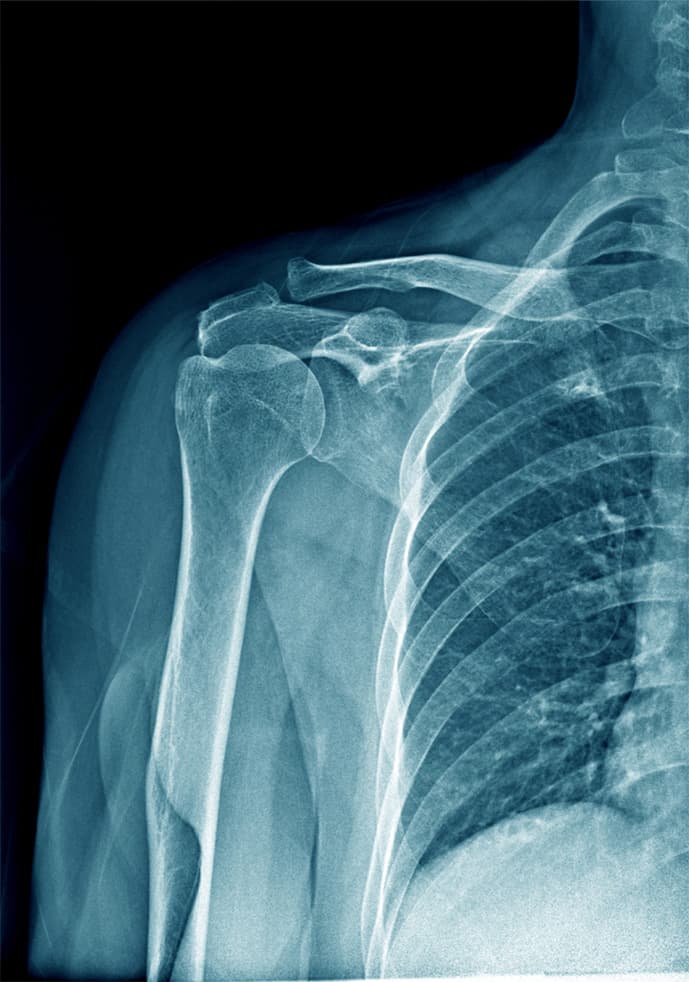

Esperto anche in traumatologia dello sport, mi dedico a trattamenti avanzati per la spalla, con un focus sulla chirurgia artroscopica e l'ortobiologia, utilizzando PRP e cellule staminali per un recupero ottimale.